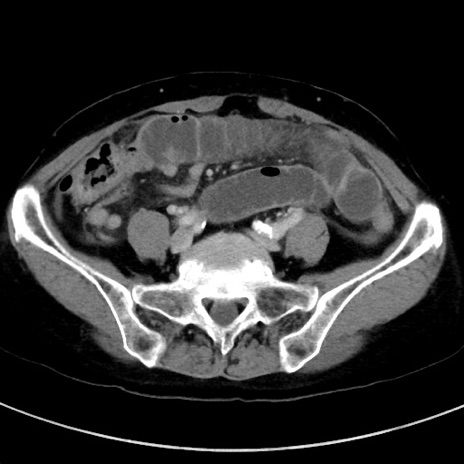

症例23(横断像)

【症例】70歳代女性

【主訴】下腹部痛・嘔吐

【現病歴】2日前より腹痛あり。昨日嘔吐あり。症状改善しないため来院。

【既往歴】胃GISTに対して胃部分切除後。

【身体所見】BT 37.1℃、BP 128/77mmHg、腹部:平坦・軟、下腹部に圧痛あり。

【データ】WBC 10200、CRP 0.31